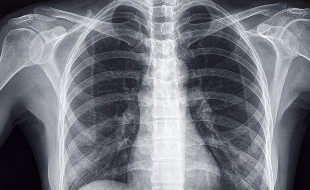

MRI、CT、X線、骨密度測定装置などの高度医療機器を完備。

精密な画像診断により、早期発見・早期治療が可能。

• レントゲン撮影

• CT検査

• MRI検査等